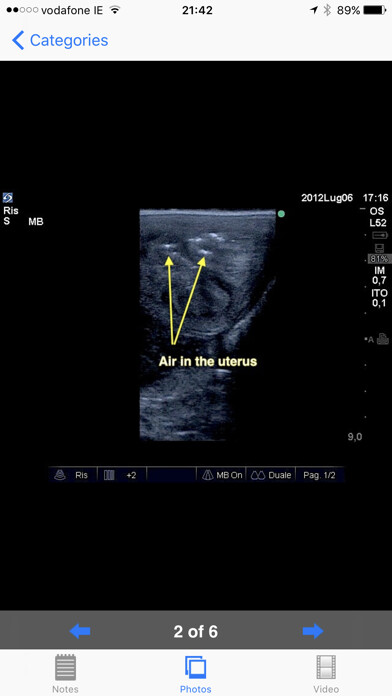

Equine reproductive ultrasound is a comprehensive guide to the examination of the equine female reproductive tract.

It features high quality labeled pictures clearly demonstrating the important structures.

Furthermore, every phase and condition discussed features high quality ultrasound Video loops.

Developed by Dr Marco Livini, past coordinator of SIRE (Italian Society of Equine Reproduction) and past President of SIVE (Italian Society of Equine Practitioners), the App provides extensive notes, still ultrasonographic images and videos.